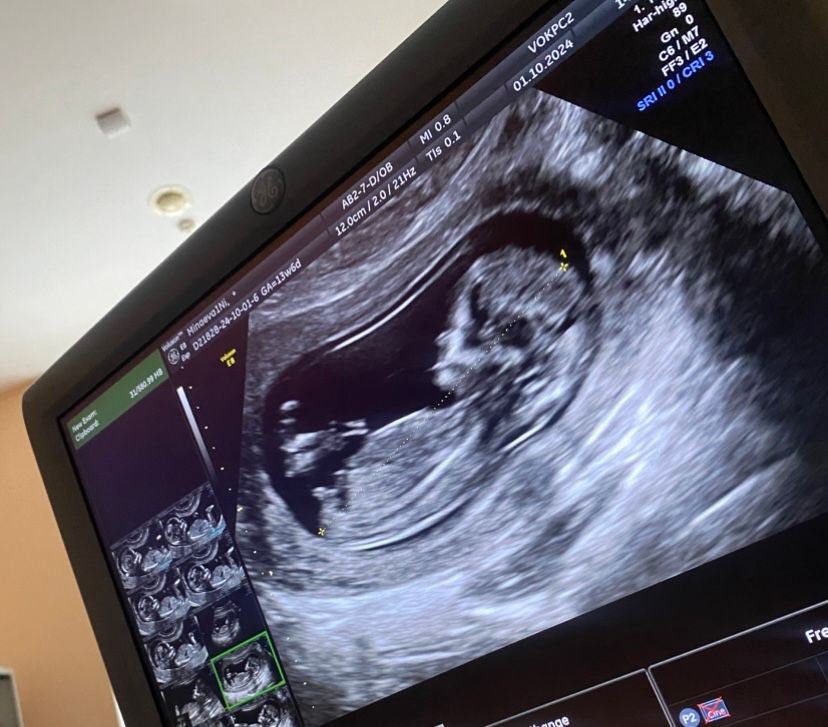

Девочки,прилагаю фото с 1ого скрининга в 13 недель ,врач сначала сказала девочка,потом что все таки мальчик,может кто видит кто будет😁хочу сходить на узи в 18 недель как думаете может врач уже сказать на 100%

По половому бугорку больше на мальчика похоже

Мальчик. Красным обвела снизу спинку и красным подчеркнула половой бугорок. Видите эту белую линию? Вот эта линия перпендикулярна спинке. У вас мальчик)

Мне в частной клинике говорили, что до 20 недели пол может быть установлен не точно, т.к. у мальчиков еще не вышли яички, поэтому бывает так, что на девочку могут подумать, что мальчик из-за узла пуповины, например. А на мальчика могут подумать , что девочка. Я делала на 21 неделе, было явно видно половой орган мальчика и по бокам яички) На дочку делала узи в 16 недель, пол точный, но у меня узист был проверенный, очень опытный

В 18 недель однозначно скажут. Можно сдать кровь на определение пола, это 100%